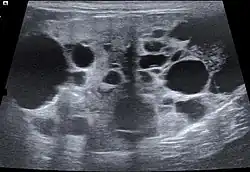

The ultrasound examination allows morphological changes in the kidneys in more detail. In addition to changes in size and shape, renal cysts, localized (focal) organ damage, water sac kidneys and urinary retention as well as tumors can also be visualized. Hardly defined (diffuse) organ changes are accompanied by changes in echogenicity, but can only rarely be assigned to defined diseases.[22] Pulsed Wave Doppler" can also be used to detect circulatory disorders.[23] Calcification (nephrocalcinosis) is also common in chronic kidney disease and can also be detected sonographically.[24]